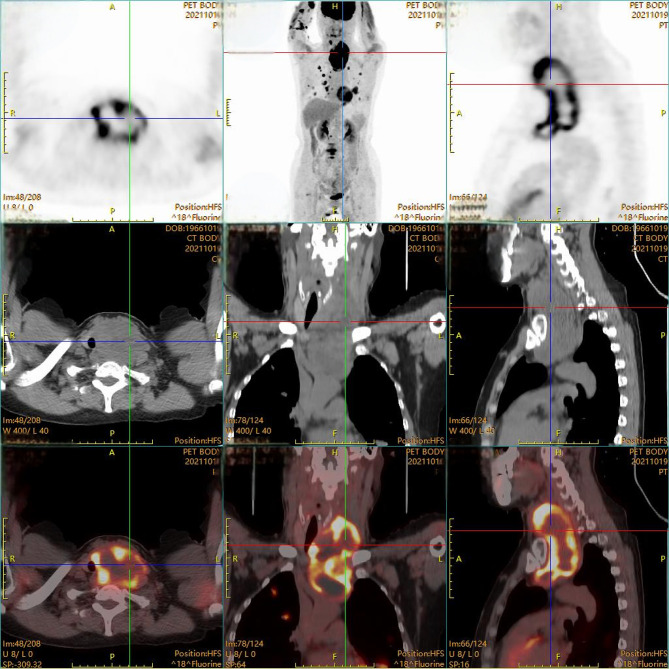

Case presentation: A 55-year-old female with no prior thyroid disease was diagnosed with advanced ATC after a routine check-up revealed a neck mass. She presented with a tumor compressing the trachea, recurrent laryngeal nerve, and carotid sinus, accompanied by Horner's syndrome. Fine-needle aspiration confirmed anaplastic sarcoma. After a multidisciplinary consultation, the patient was treated with anlotinib, tislelizumab, and albumin-bound paclitaxel, resulting in significant tumor shrinkage and symptomatic relief. However, due to financial constraints, treatment was discontinued. One month later, the tumor rapidly progressed, leading to tracheal compression and asphyxiation, causing her death.